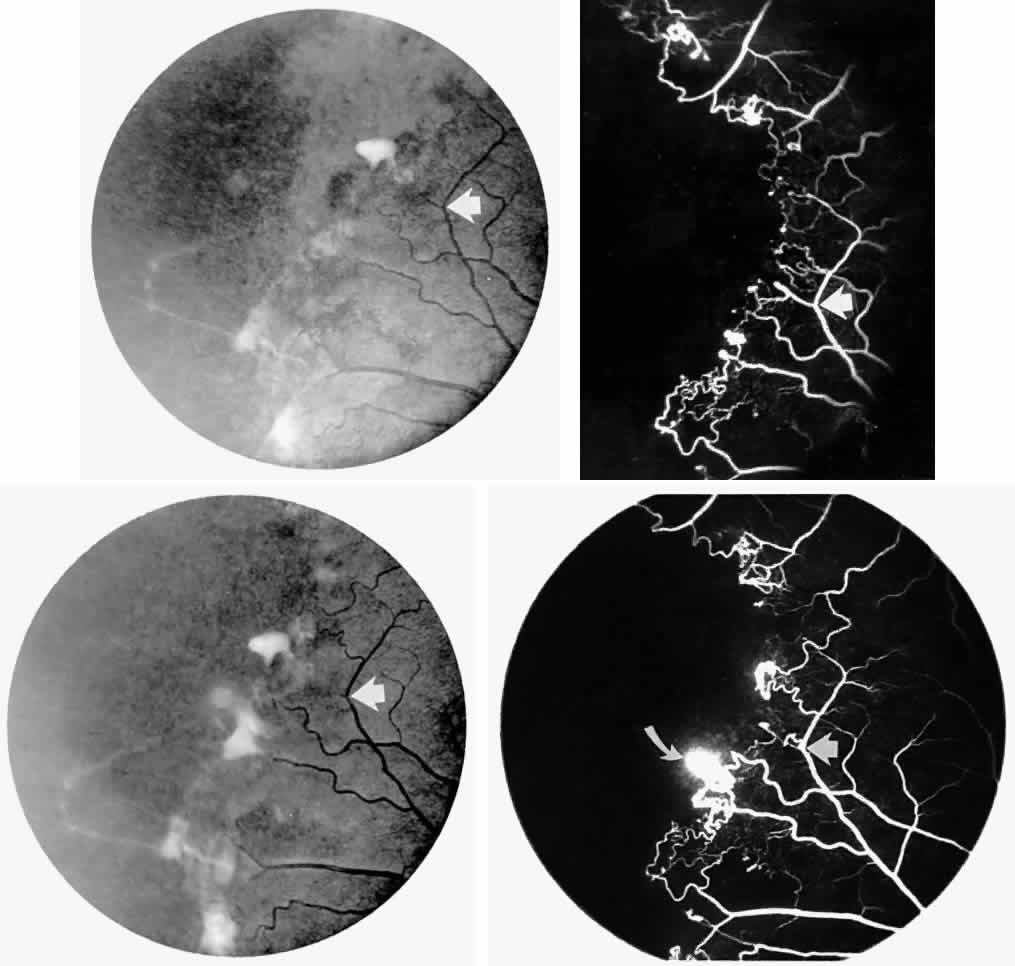

STAGE III: PRERETINAL NEOVASCULARIZATION (PROLIFERATIVE SICKLE RETINOPATHY). “Sea fan”-shaped neovascularization typically develops on the venular side of an arteriolar-venular anastomosis, mimicking the normal development of retinal capillaries (Fig. 24).125 A lowered oxygen tension and angiogenic factors released on the venular side may be the stimulus for neovascular growth.125,126 In most instances, the direction of growth is toward the ora serrata, from the perfused retina toward the nonperfused retina. Presumably, this represents an abortive attempt to revascularize the nonperfused retina, initiated by vasoproliferative factors.

Fig. 24. A. Photograph of the peripheral retina, demonstrating several small fibroglial membranes. B. Fluorescein angiogram corresponding to A, showing multiple arteriolar-venular anastomoses with early sea fan formation. C. Photograph of the same area 2 years later demonstrates more fibroglial membranes. D. Fluorescein angiogram corresponding to C shows new sea fans caused by an arteriolar-venular anastomosis (curved arrow). Large arrow (A through D) identifies corresponding arteriolar bifurcation.

The characteristic neovascular lesions of PSR are called sea fans because they resemble the marine invertebrate Gorgonia flabellum.70 They tend to occur more commonly in the temporal periphery, but they have been reported to occur in the temporal macula in the presence of extensive nonperfusion.130,133 Initially they grow on the surface of the retina, but they often become elevated into the vitreous and adhere to a partially detached posterior hyaloid.114 It may be difficult to visualize small sea fans ophthalmoscopically; however, fluorescein angiography clearly demonstrates leakage of dye into the vitreous (Fig. 25). The feeding arteriole is usually more tortuous than the draining venule (Fig. 26). Early on, the neovascular lesion is fed by a single arteriole and drained by a single venule, but with time, additional arterioles and venules become arborized within the lesion (Fig. 27).129 Growth of the sea fan often occurs circumferentially, rather than radiallyÜmh- 1Ý, toward the ora serrata. Progressive circumferential growth may lead to neovascular lesions extending around the entire periphery. As it matures, a white fibroglial mantle often covers the neovascular tissue (Color Plate 2B).

Fig. 25. Fluorescein angiogram of early proliferative sickle retinopathy arising from an arteriolar-venular anastomosis in an area of irregular peripheral capillary border. Note that this area of qualitatively abnormal peripheral capillary border is in the same eye with a qualitatively normal peripheral retinal vasculature, as demonstrated in Figure 23.

Fig. 26. A. Arterial filling phase of the fluorescein angiogram of a sea fan demonstrates tortuosity of the feeding arteriole. B. Early arteriolar-venular filling phase demonstrates straightening of the draining venule. Note that this sea fan is adjacent to the qualitatively normal peripheral retinal vasculature demonstrated in Figure 23.

Fig. 27. A. Photograph of sea fan neovascularization with hemorrhages at the margins and a white line demarcating perfused and nonperfused retina. B. Fluorescein angiogram shows multiple feeding arterioles and draining venules.